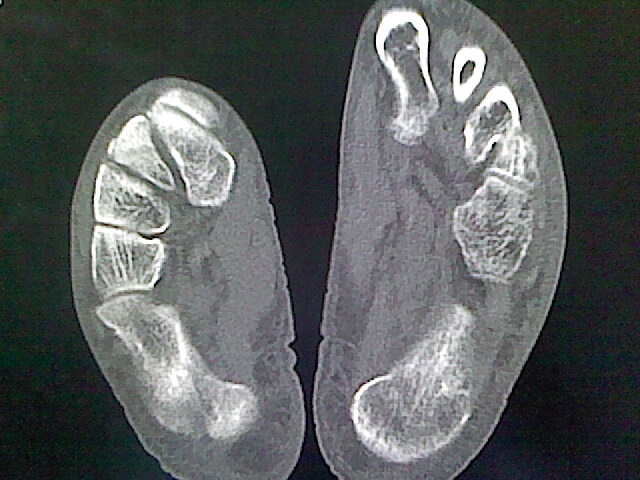

标题: CT16814:男,76岁,左小腿疼痛,不能站立 大家给看看 [打印本页]

男,76岁,左小腿疼痛,不能站立

本例骨质改变主要表现为滑膜或韧带区的骨侵蚀融解(胫腓联合区骨质破坏无硬化边),距骨后部骨质破坏区有硬化边及死骨样改变.所以,本例考虑关节结核可能性大,绒毛膜结节性滑膜炎多发于中年,且极少见于膝髋以外的关节,骨质硬坏也以压陷吸收为主,有明显的硬化边,骨膜增生呈结节状(可以mr鉴别),所以本例暂除外.

另不除外可引起相似表现的其他炎症如布氏杆菌性关节炎等